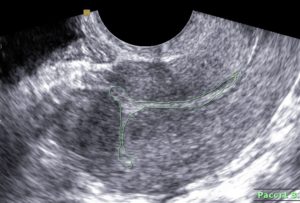

Большое внимание уделяется внешнему виду рубца. Его толщина не должна быть меньше 5 мм. На изображении он хорошо различим и выглядит как тонкая темная полоска. Вариацией нормы считается и шрам толщиной 3,5 см.

В идеале рубец должен состоять из мышечной ткани, которая более темная на снимке. У некоторых женщин присутствует соединительная ткань. На изображении возле шва имеется небольшое количество светлых участков.

Несостоятельным считается шов, толщина которого меньше 1,5 мм. Возле рубца имеются неровности и несросшаяся ткань. Сам рубец состоит преимущественно из соединительной ткани.

На снимке такие швы выглядят неровными и размытыми. Четкая темная полоска отсутствует (возможно прослеживание белой полосы). В области рубца наблюдается большое темное пятно.